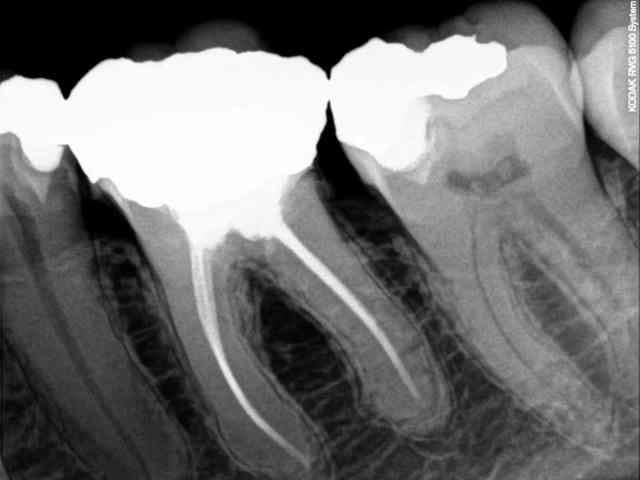

Radio pré-bourde :

R1 umjaml - Eugenol